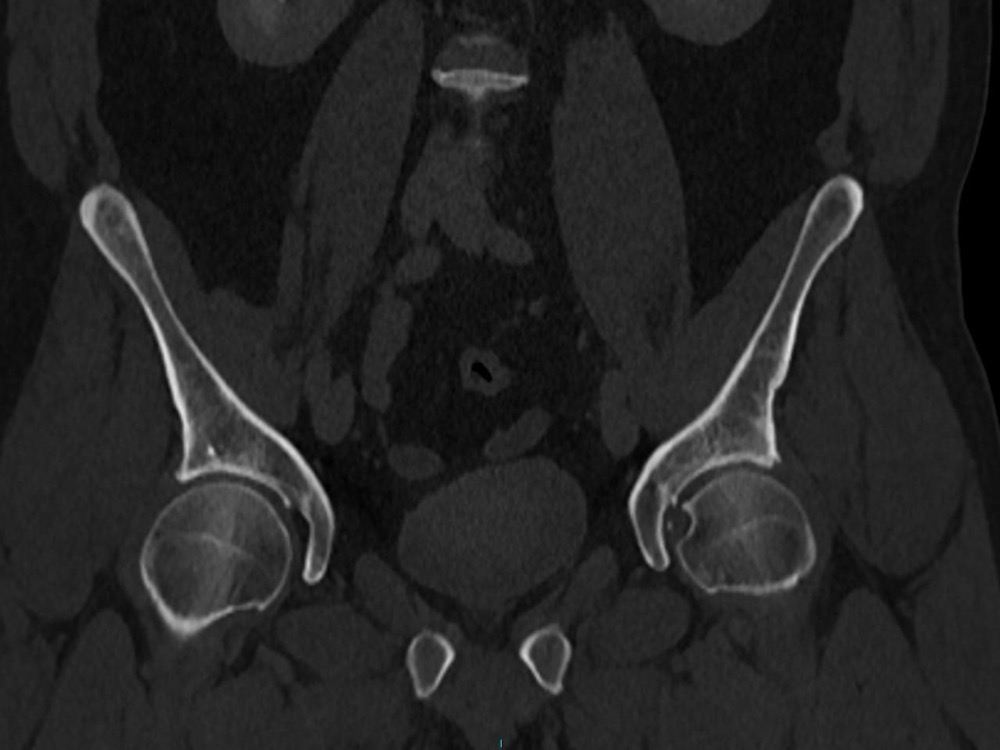

Bone Club

Olivia Fortucci 11/01/2023